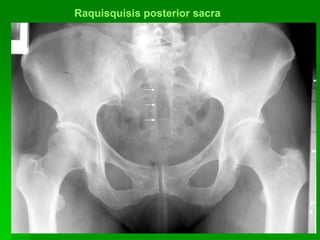

Raquisquisis posterior sacra

Calcificaciones vasculares